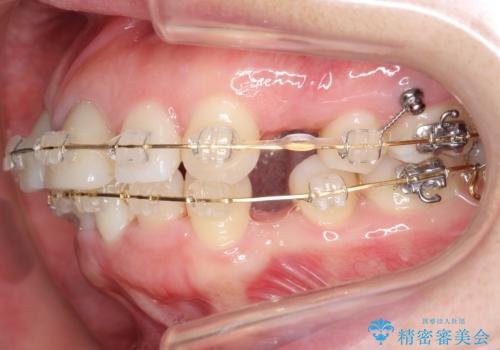

治療途中

前歯を下げるために、上下左右の小臼歯を抜歯することになりましたが、すでに前歯の角度を不自然に作ってあるため、

もう一度前歯を元の角度に被せ直してから仮歯で矯正を行いました。

矯正治療前に、一旦、引っ込めた前歯の角度を元に戻してから(出っ歯の仮歯をもう一度つけました・・・!)矯正しました。